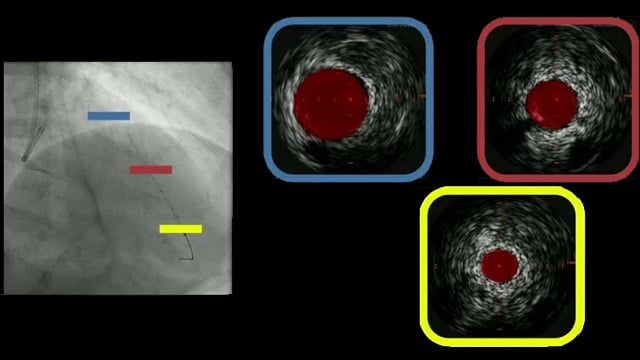

Intracoronary imaging guidance in challenging PCI scenarios

20 May 2026 – From EuroPCR 2026

This session highlights the critical role of intracoronary imaging, particularly IVUS, in guiding complex percutaneous coronary interventions. It presents techniques such as IVUS-guided puncture of neo-ostia, stent implantation for ostial lesions, and innovative procedural methods like the Heart POTTER technique, underscoring the importance of precise imaging...